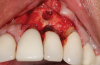

This is where the treatment became challenging. First, a curette was used to attempt to remove the granulation tissue from around the apex of the implant circumferentially. This was a difficult endeavor, especially on the palatal aspect of the site. Following curettage, an 810 nm diode laser (NV® PRO3, DenMat [alternatively: Picasso+, AMD Lasers; Gemini, Ultradent]) was used to treat the apical portion of the implant. After the laser tip was initiated using dark occlusal paper (Figure 4), it was used to debride the remaining necrotic tissue and decontaminate the entire site, reducing the bacterial count (Figure 5 and Figure 6).

(3.) An envelope reflection was made with no vertical incisions, exposing the entire bony defect affecting the apical portion of the stable implant.

Figure 3